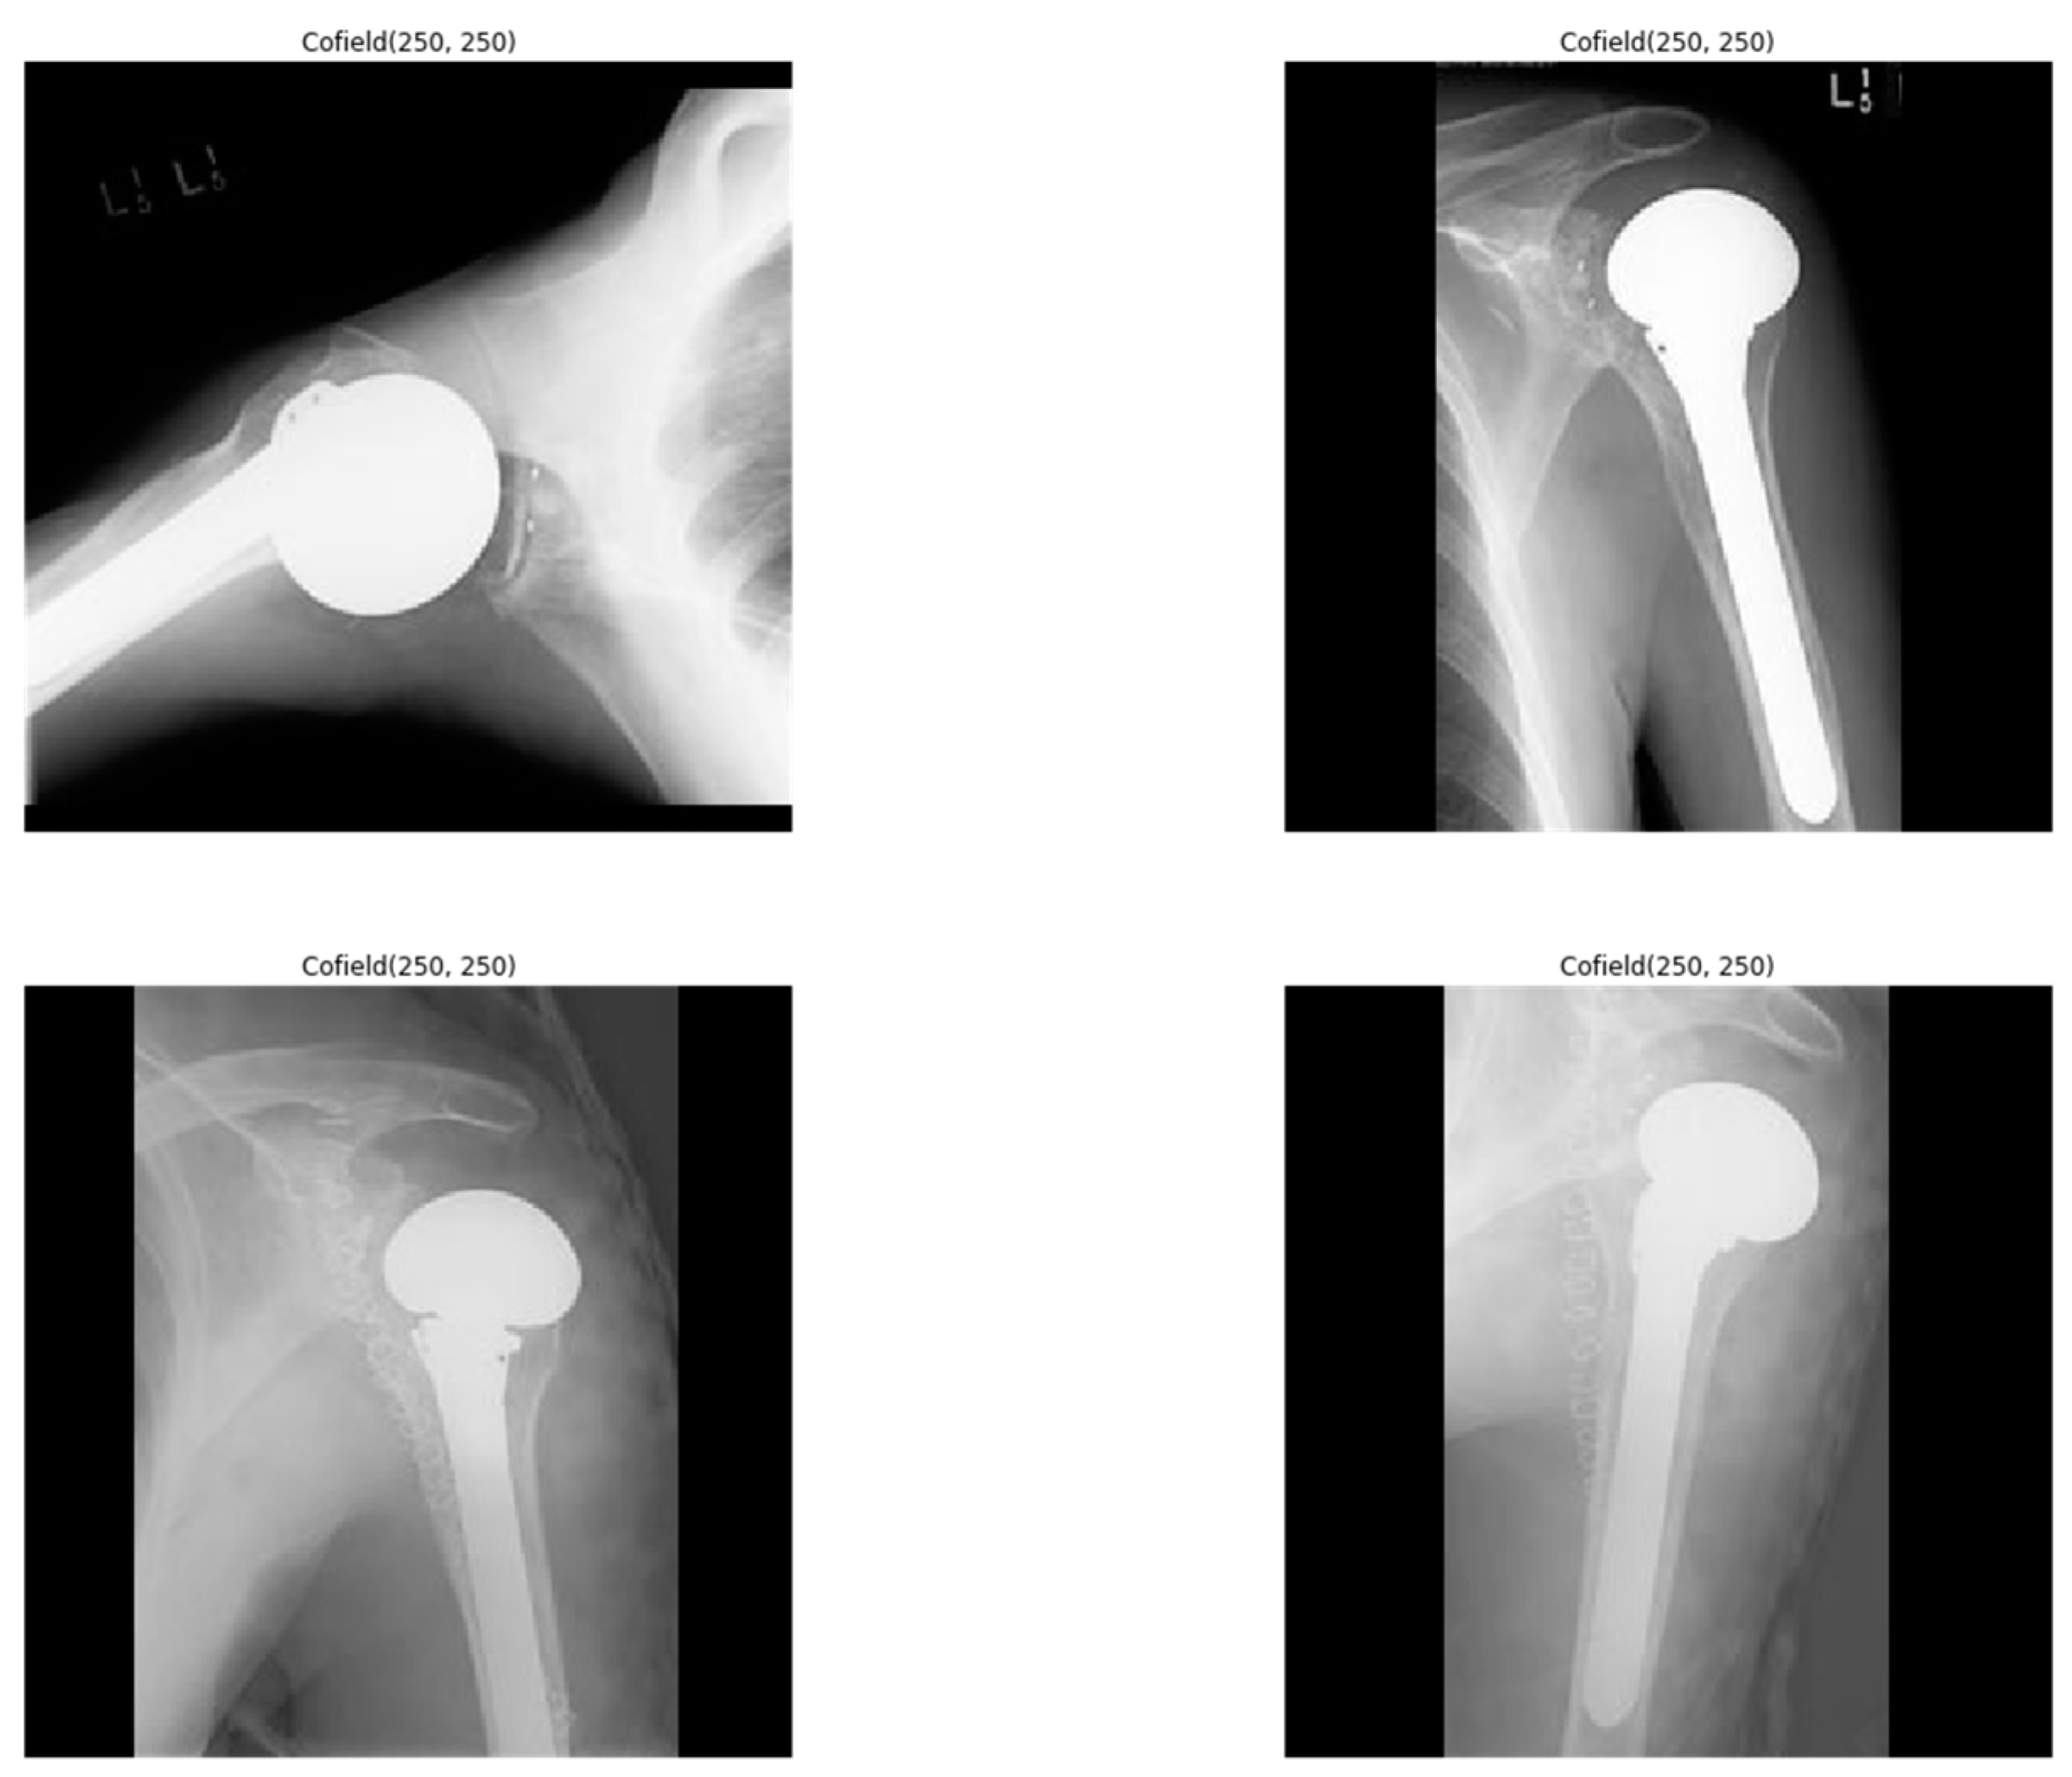

2.1. Dataset

- UCI Machine Learning Repository, Shoulder Implant X-ray Manufacturer Classification Dataset. Available online: https://archive.ics.uci.edu/mL/datasets/Shoulder+Implant+X-ray+Manufacturer+Classification (accessed on 20 February 2021).